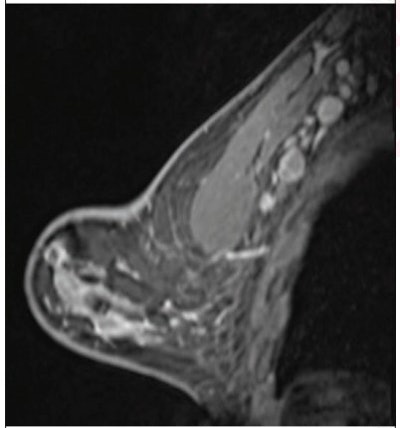

(Above) 55-year-old woman who underwent screening mammogram and ultrasound seven days after first COVID-19 vaccination dose. Screening mammogram and US demonstrated unilateral left axillary lymph node with cortical thickness of 5 mm on ultrasound (not shown). BI-RADS category 0 was assigned. Ultrasound from diagnostic work-up performed seven days later showed no change in lymph node size. BI-RADS 3 was assigned. (Below) 41-year-old woman who underwent high-risk screening breast MRI 15 days after first COVID-19 vaccination dose. Sagittal T1-weighted fat-saturated contrast-enhanced MRI shows extensive unilateral left level I-II axillary adenopathy. BI-RADS 3 was assigned. Images and captions courtesy of the American Roentgen Ray Society.